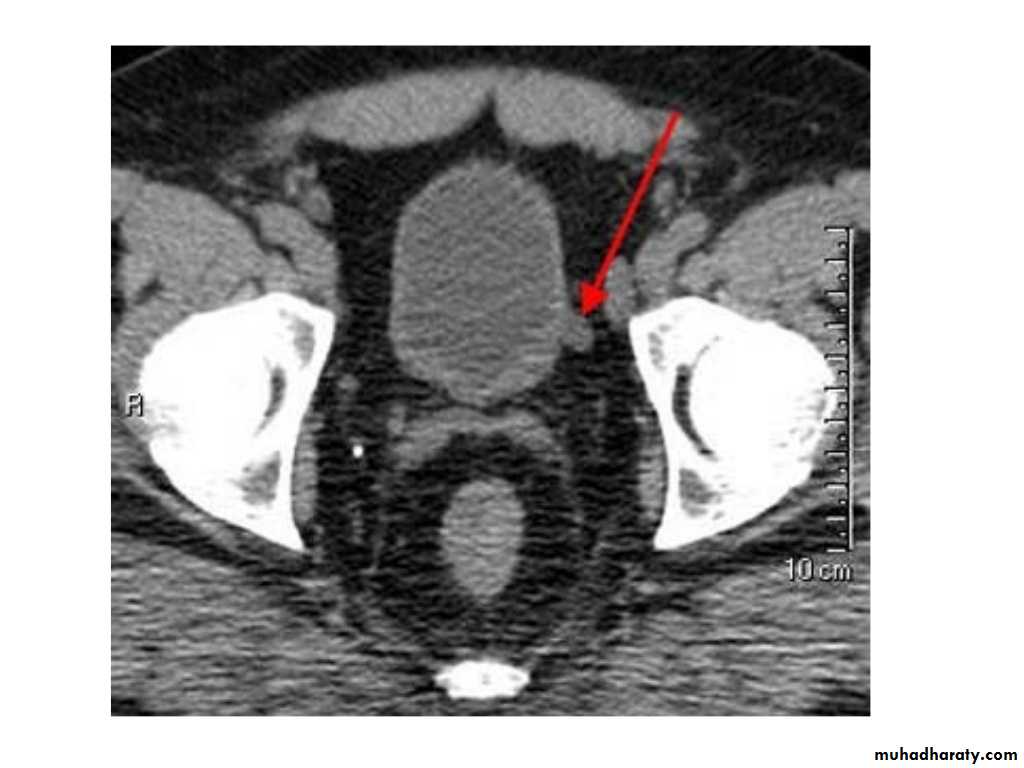

IVU shows

1. The kidneys at low position .2.Close to the spine with long axis parallel to the spine

3. Malrotation manifested by medially directed calyces.

4- The renal pelvis and ureters are anterior and lateral in position.

5- Hydronephrosis and calculi highly associated.